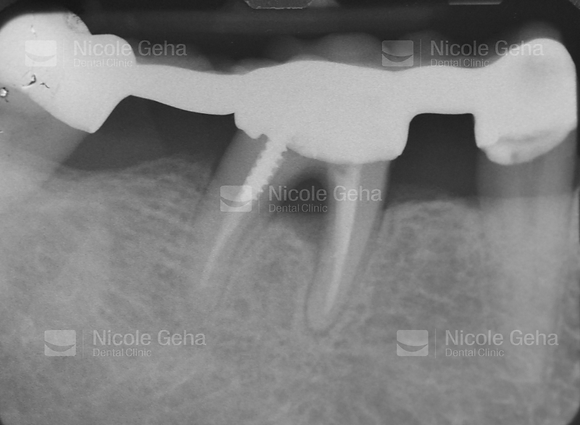

SINGLE IMPLANT

Implant's healing phase